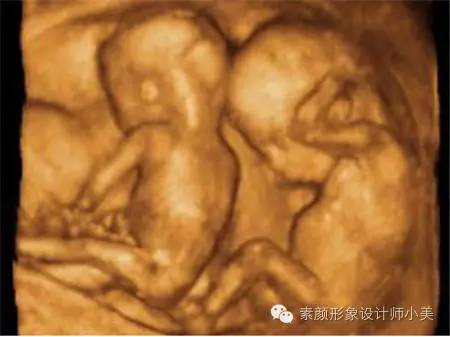

23周的胎儿看起来已经很像一个缩小的婴儿了,他(她)的身长大约20厘米,体重在450克左右。但由于皮下脂肪尚未产生,这时胎儿的皮肤是红红的,而且皱巴巴的,样子像个小老头。皮肤的折皱是给皮下脂肪的生长留有余地。